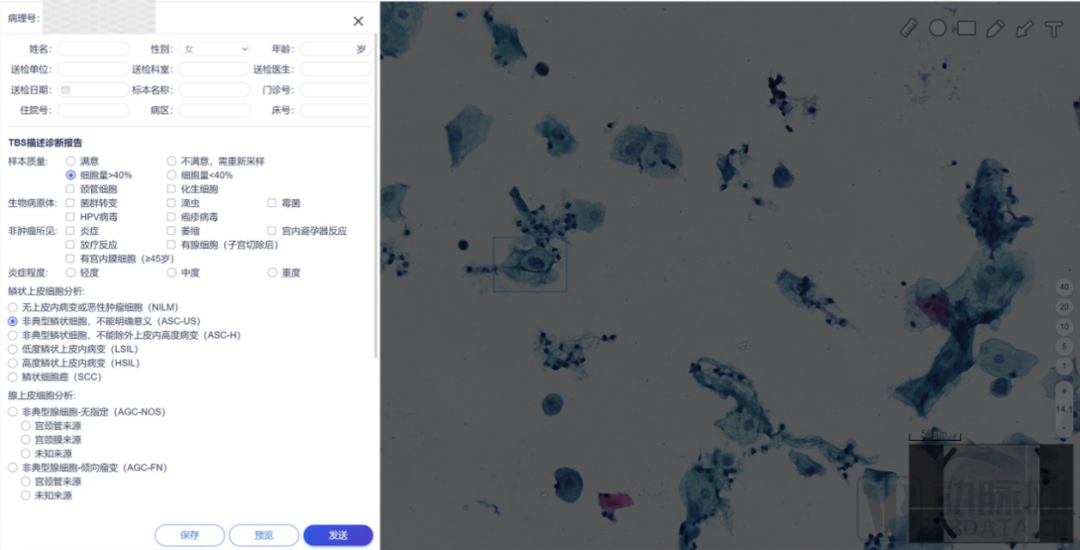

数字化病理科建设模块介绍

数字化建设模块图

来源:蛋壳研究院